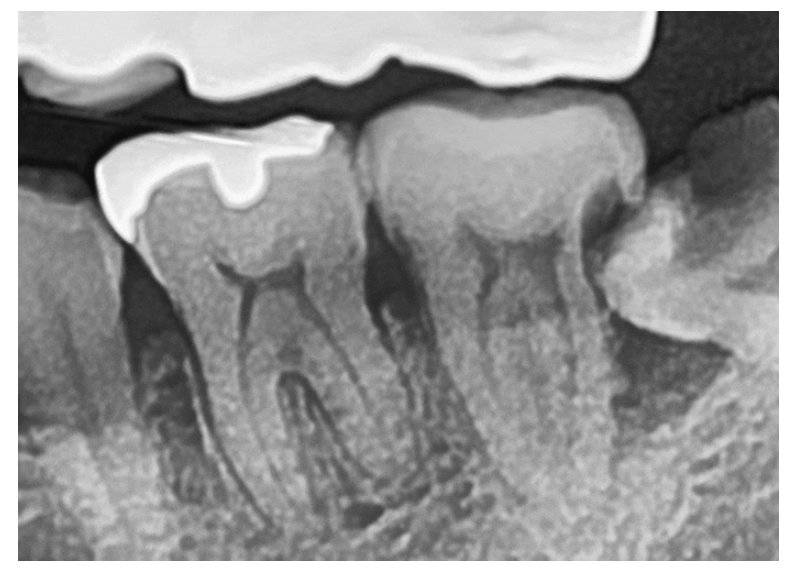

엑스레이 사진은 치아가 썩은 충치 부분을

투과할 수 있어 까맣게 나타나는데요.

구강 내 사진에서는 잘 눈에 띄지 않지만

이렇게 방사선 사진을 촬영해 보면

더욱 발견하이 용이하답니다.

엑스레이 사진에 표시한 부분들이 충치인데,

오른쪽 아래 두번째 어금니

왼쪽 아래 두번째 어금니

왼쪽 아래 사랑니

이렇게 3개의 치아에 심각한 충치를

발견할 수 있었습니다.

사랑니와 더불어 두 번째 큰 어금니들 모두

발치 가능성이 아주 높아 보였고,

다른 치과에서는 발치가 필요하다는

설명도 들으신 상태였는데요.

하지만 서울바로본치과에서는

사랑니만 발치를 하고

2개의 어금니들은 신경치료를 통해

치아를 살려보기로 하였습니다!

그 다음, 어금니에 충치를 제거한 부위에

보강 재료를 쌓아 올렸고,

엑스레이 사진을 통해

체크를 해주고 있는 모습입니다.